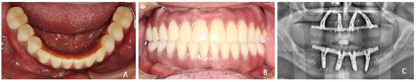

③种植临床戴牙:利用上颌加工完成的钛支架支持的义齿蜡型,螺丝固定,下颌利用原覆盖义齿修复体局部修理后口内稳固就位作为下颌托,制取咬合记录转移颌位关系。在模型上加工制作树脂修复体,上颌钛支架支持的终义齿修复体恢复至第一磨牙,下颌临时固定修复体暂恢复至第二前磨牙(图12)。戴牙完成后拍摄X线根尖片检查种植体及修复体连接密合(图13)。

(4)种植终义齿修复:下颌种植即刻固定修复后患者原因未能按时复诊,2019年2月(一期手术后24个月,下颌二次种植术后17个月)来诊,X线检查示种植体周围骨结合良好(图14)。制取下颌种植修复印模,制作钛支架支持的树脂修复体,恢复第一磨牙的咬合接触关系,行种植固定终义齿修复(图15)。

种植修复后义齿使用状况良好,经过治疗周期内多次的健康教育,患者掌握了口腔卫生理念和健康行为,口腔卫生状况改善。植体周健康状况保持良好。通过治疗恢复了相对健康的口腔环境和牙列的完整性,美学效果及咬合功能患者满意(图18)。